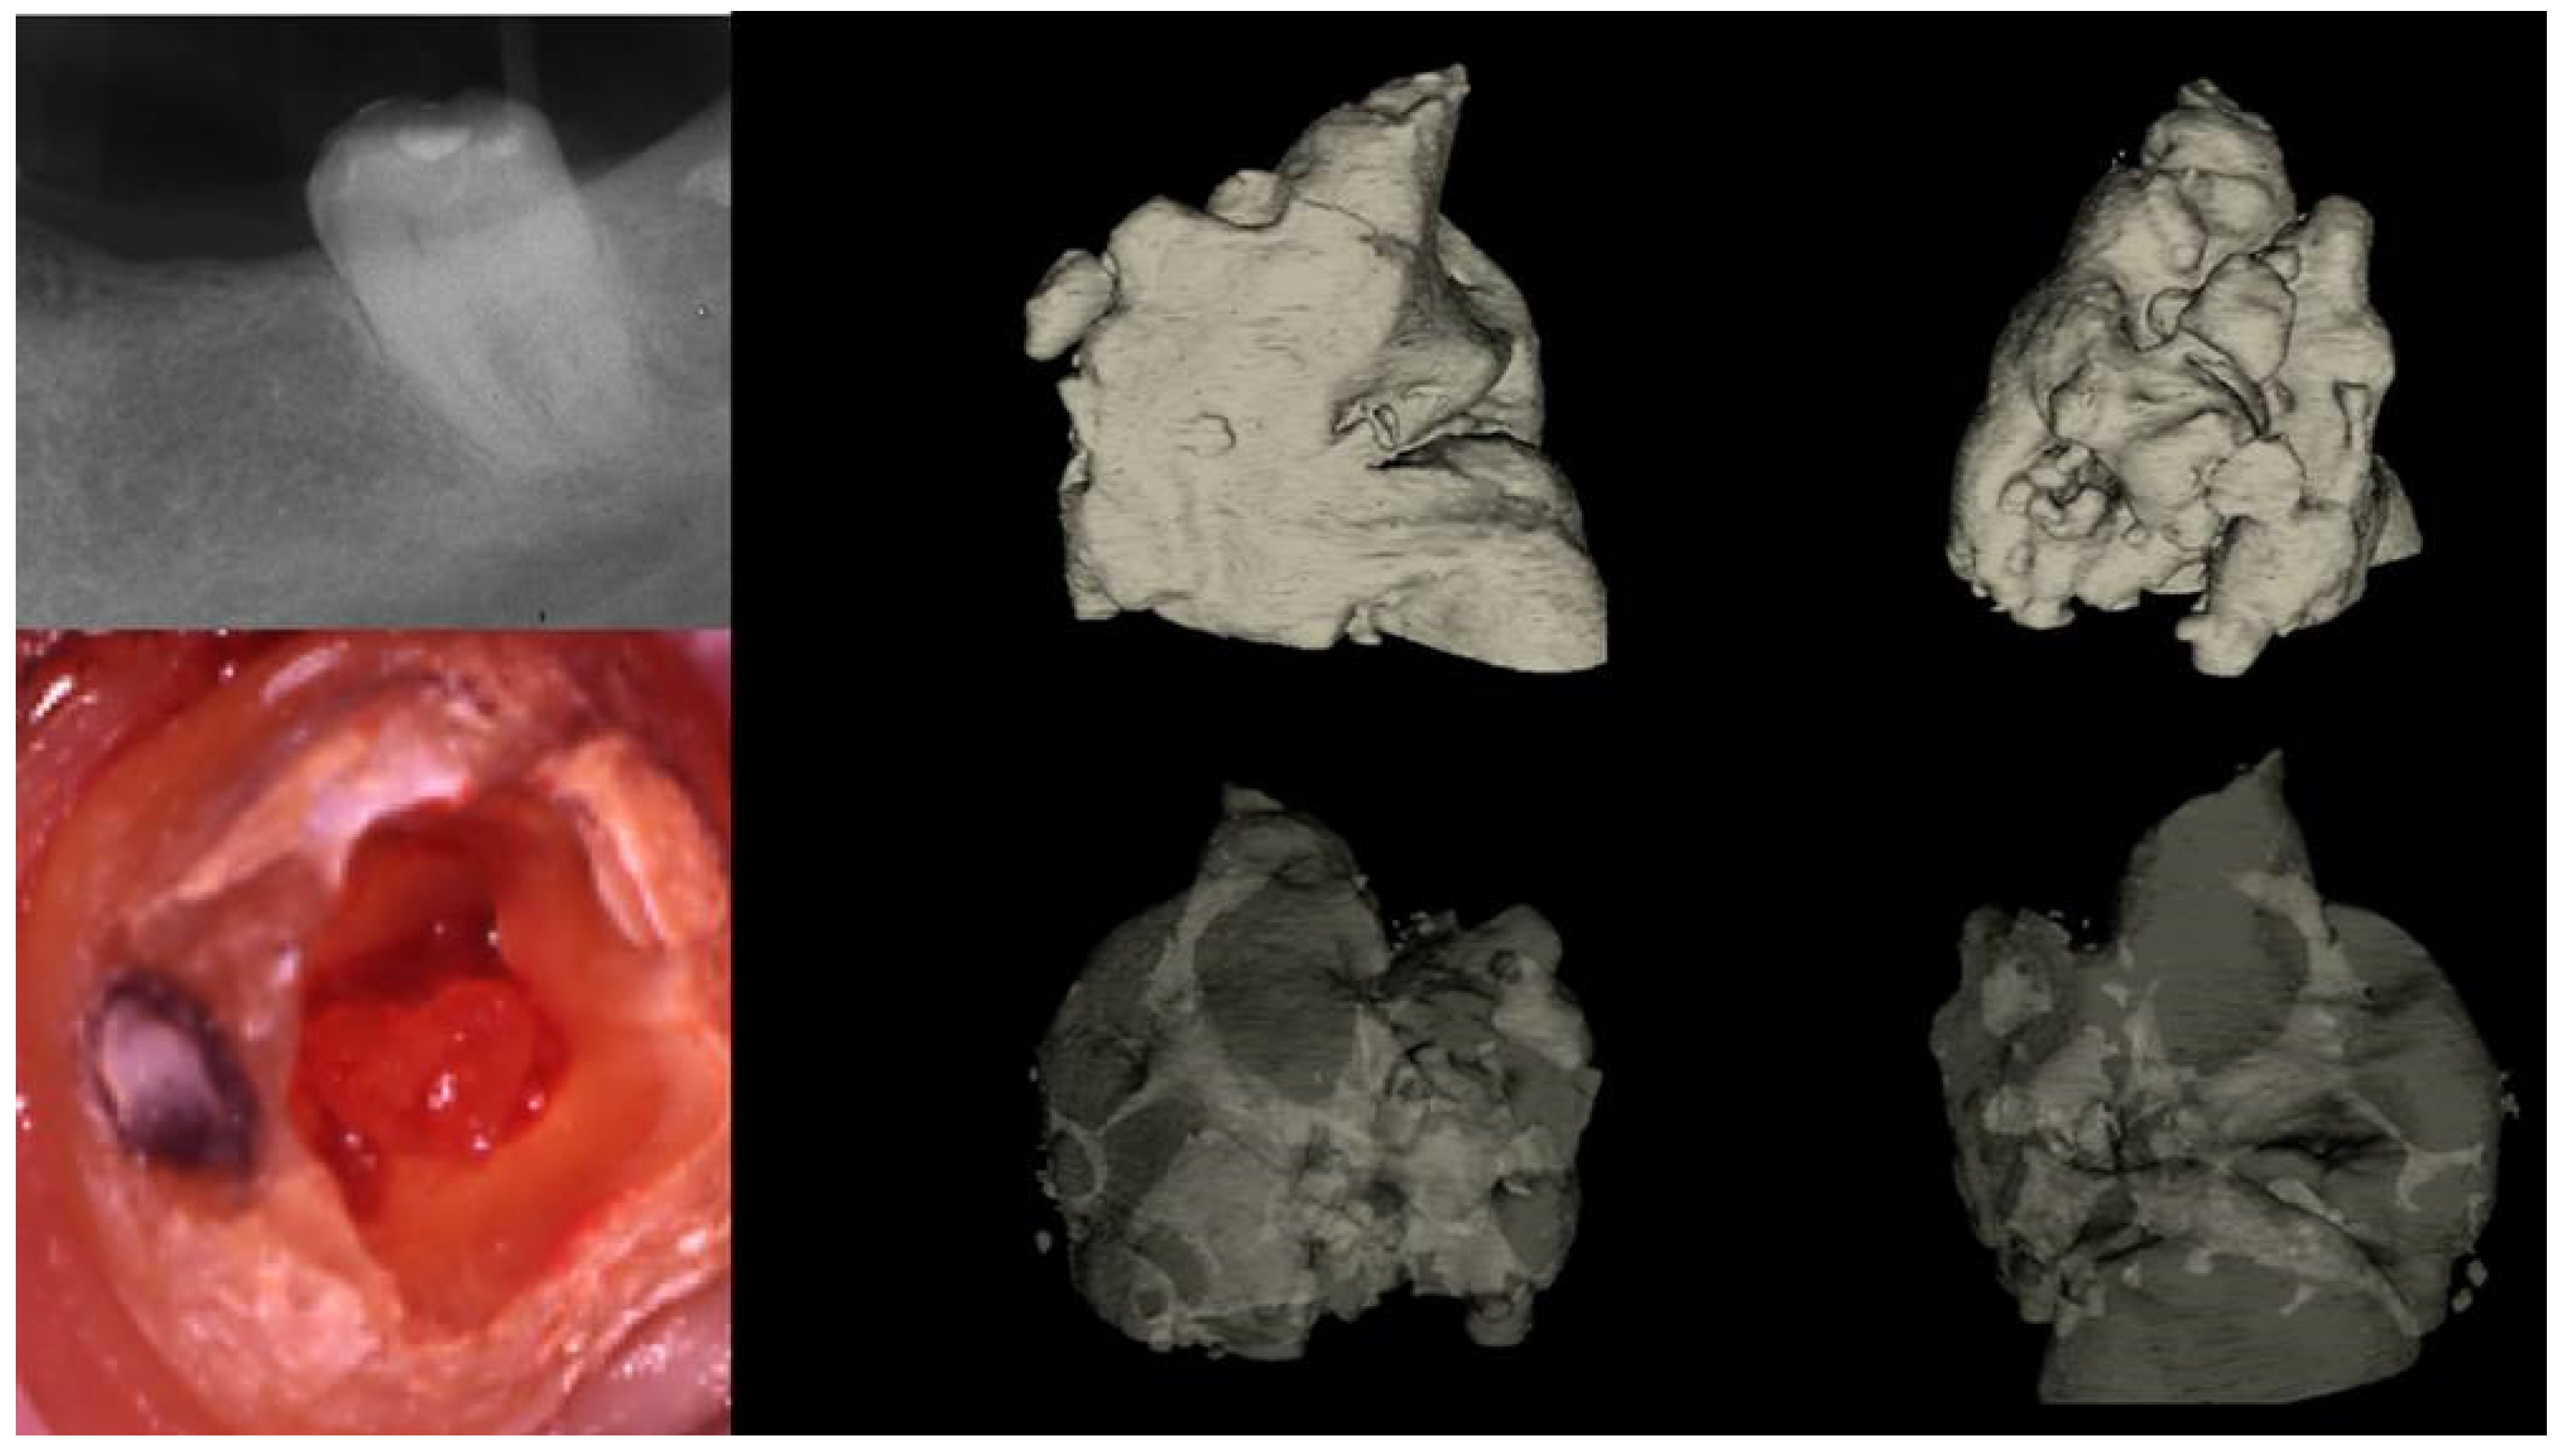

Figure 3.

Histological images of the calcified vital pulp tissue that was removed during the root canal treatment of a second mandibular molar with deep periodontal distal lesion suffering from symptomatic irreversible pulpitis. Notice the linear calcified nodules formed along the root pulp vessels. (hematoxylin eosin staining) (Histological images courtesy of prof. Domenico Ricucci).